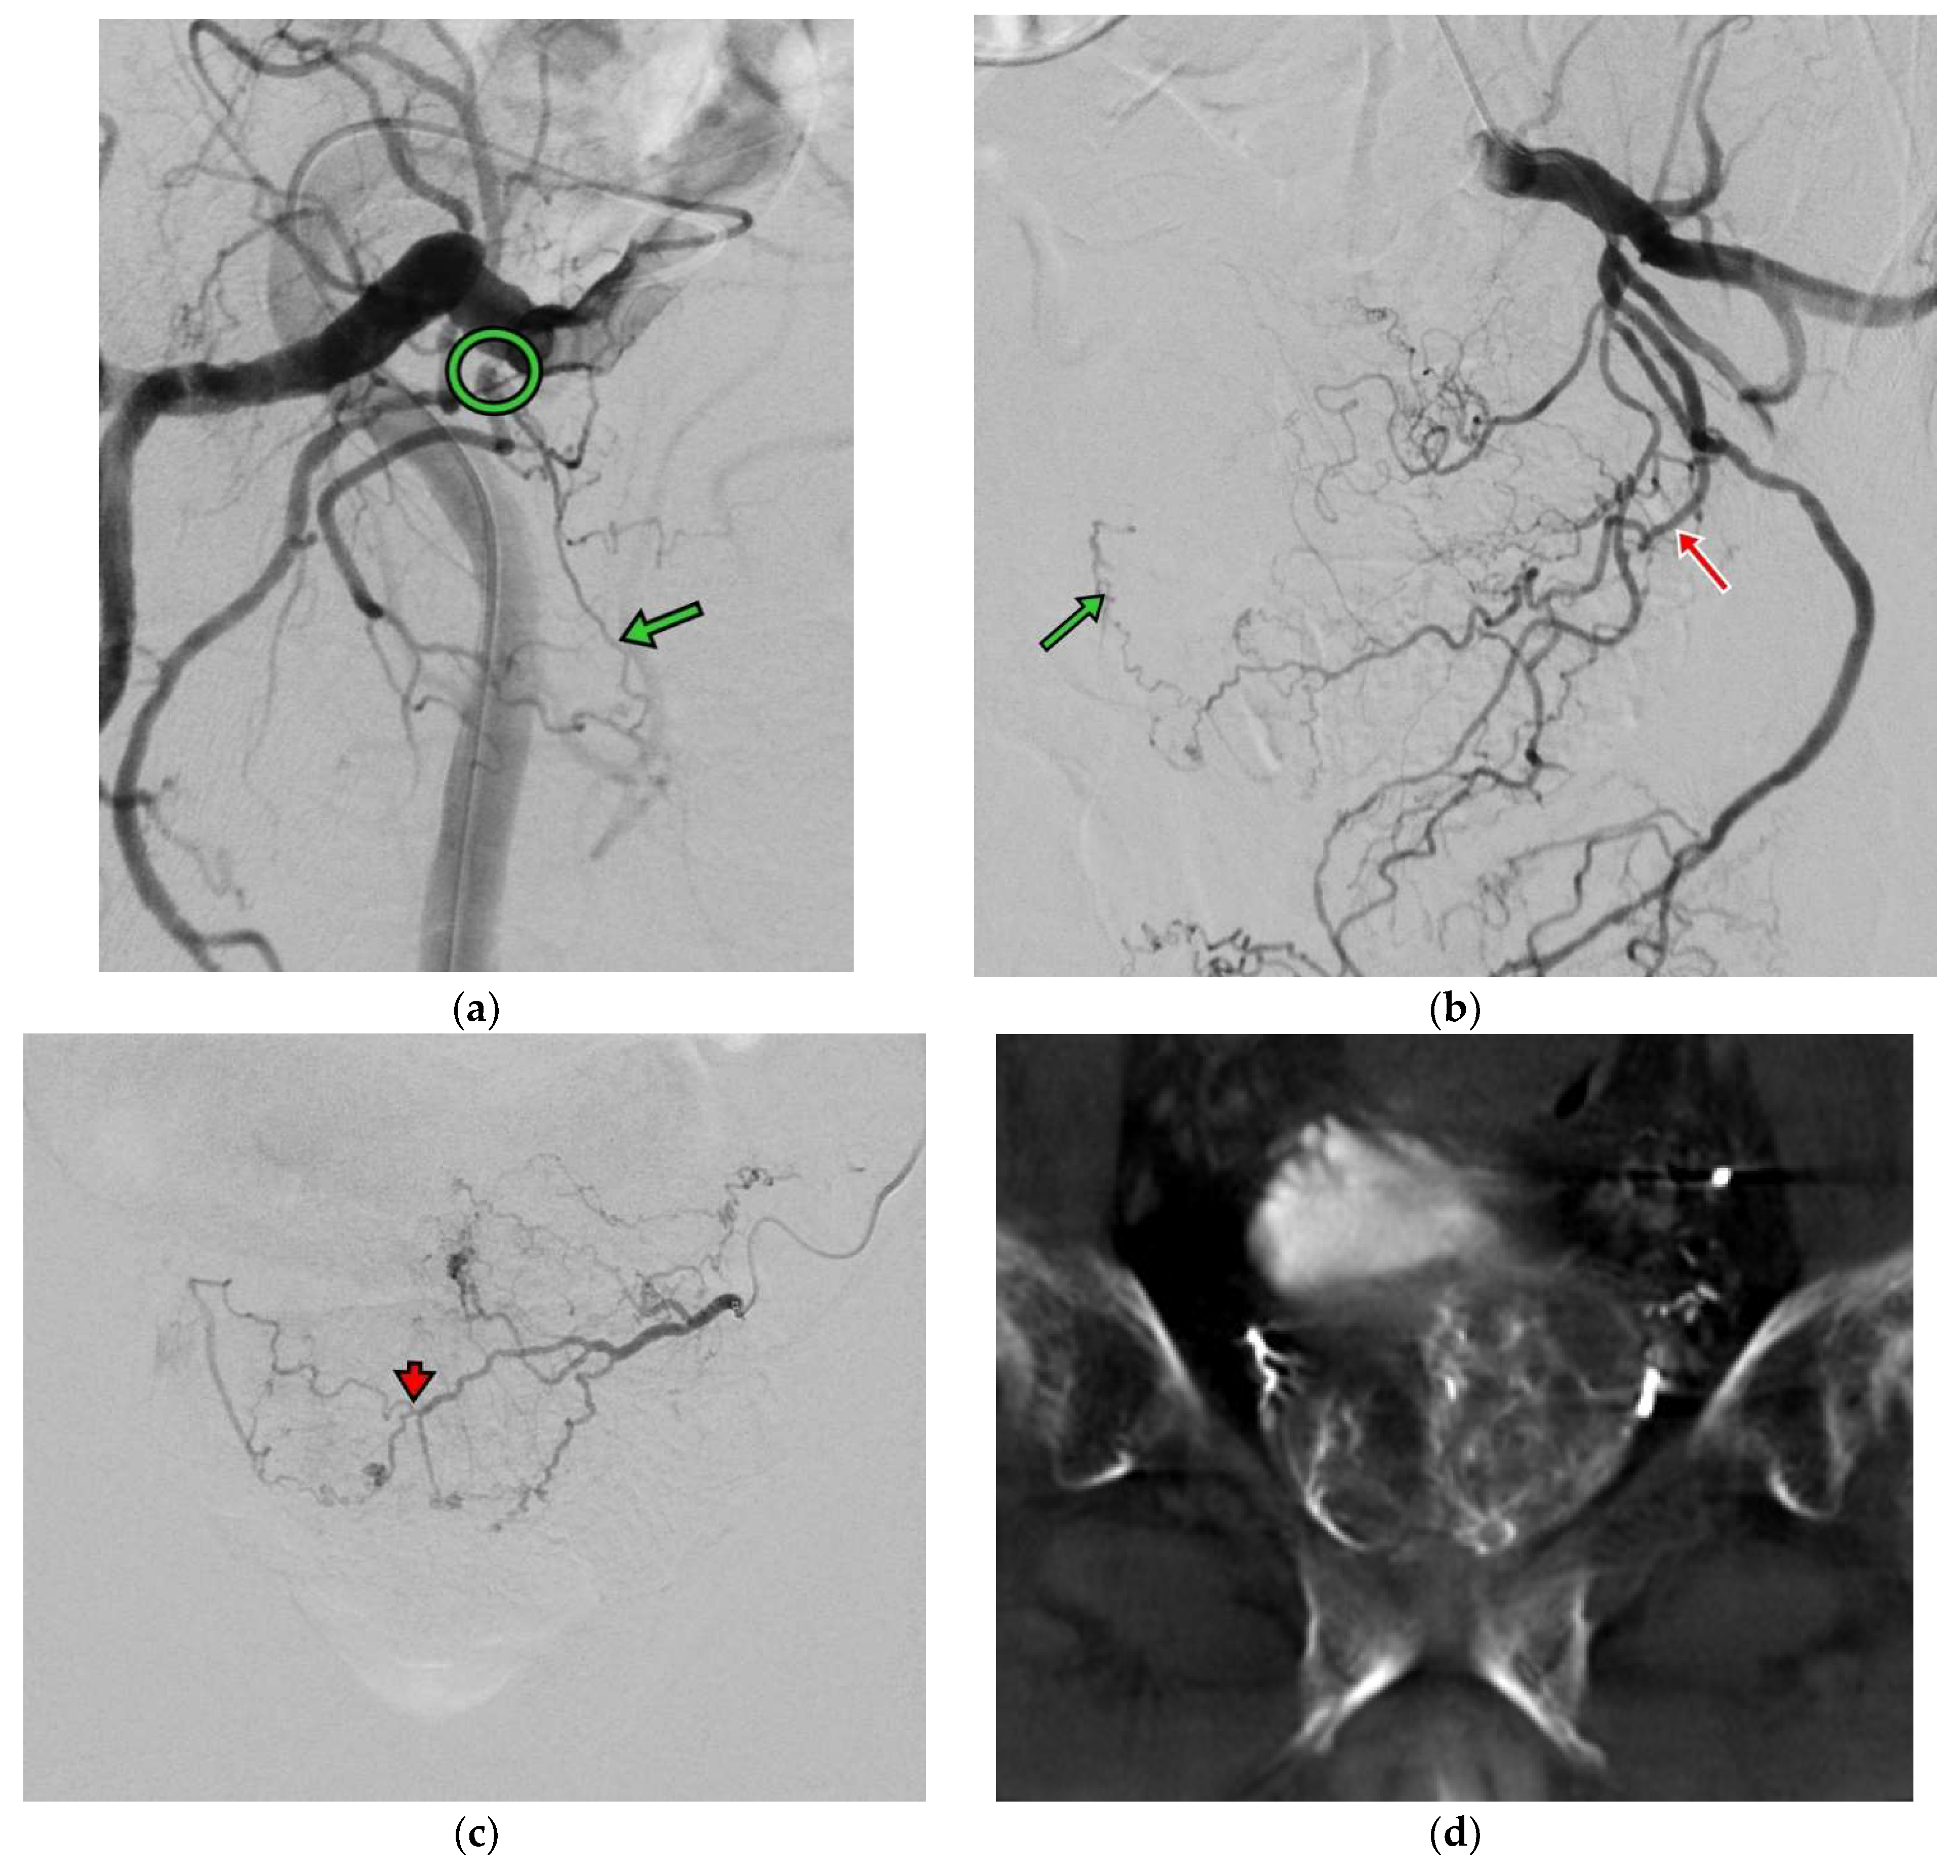

3. Results